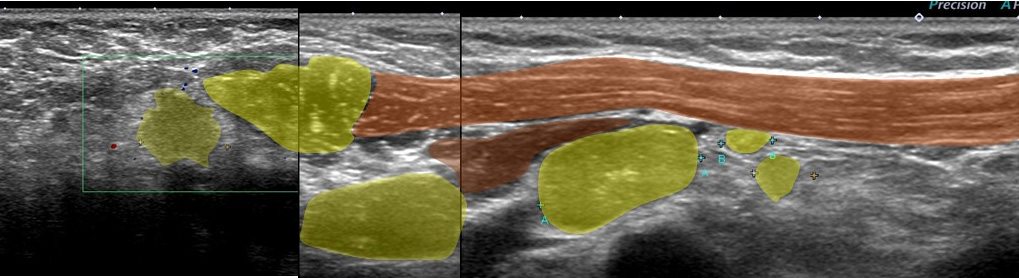

レベル2リンパ節 これが一番大きい 2㎝

形はリンパ節の形をしており「節外」では(画像上)なさそう。

大きなレベルⅡは、レベルⅢに近い部位までせり出し、その奥(図中央)にはレベルⅢが

確認できる。

←外側 (皮膚側) 内側(奥)→

これらエコーをつなぎ合わせたもの

リンパ節は黄色に表現

大胸筋(茶色)の裏に小胸筋(こげ茶色)

大胸筋の外側にリンパ節2つ、大胸筋の裏にリンパ節1個 これら3個がレベルⅠ

小胸筋裏にリンパ節(これが最大で2㎝)これがレベルⅡ

それより内側(奥)に比較的小さいリンパ節2個 これらがレベルⅢ

色分けすると 赤とオレンジ:レベルⅠ、 黄色:レベルⅡ 、赤(周囲に点線の小さいもの):レベルⅢ